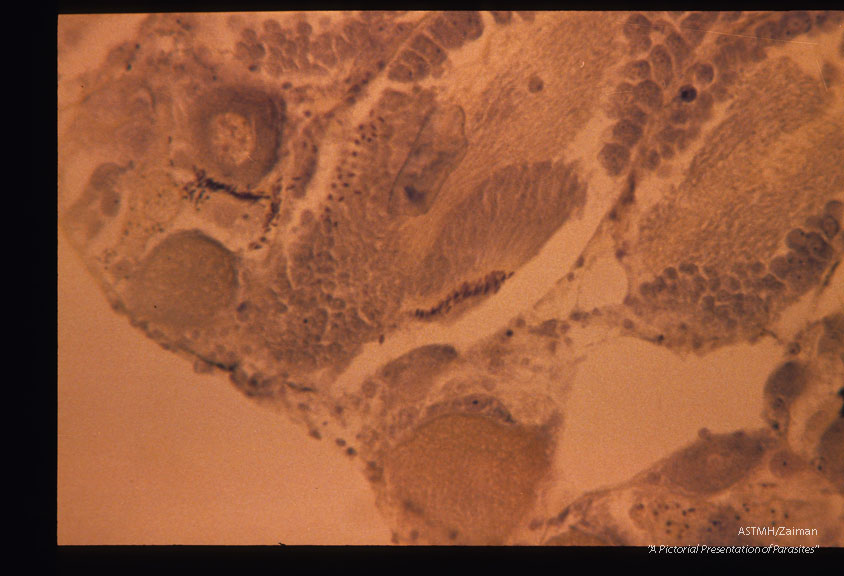

Section through normal snail liver.

Biomphalaria glabrata

Description: Section through normal snail liver.